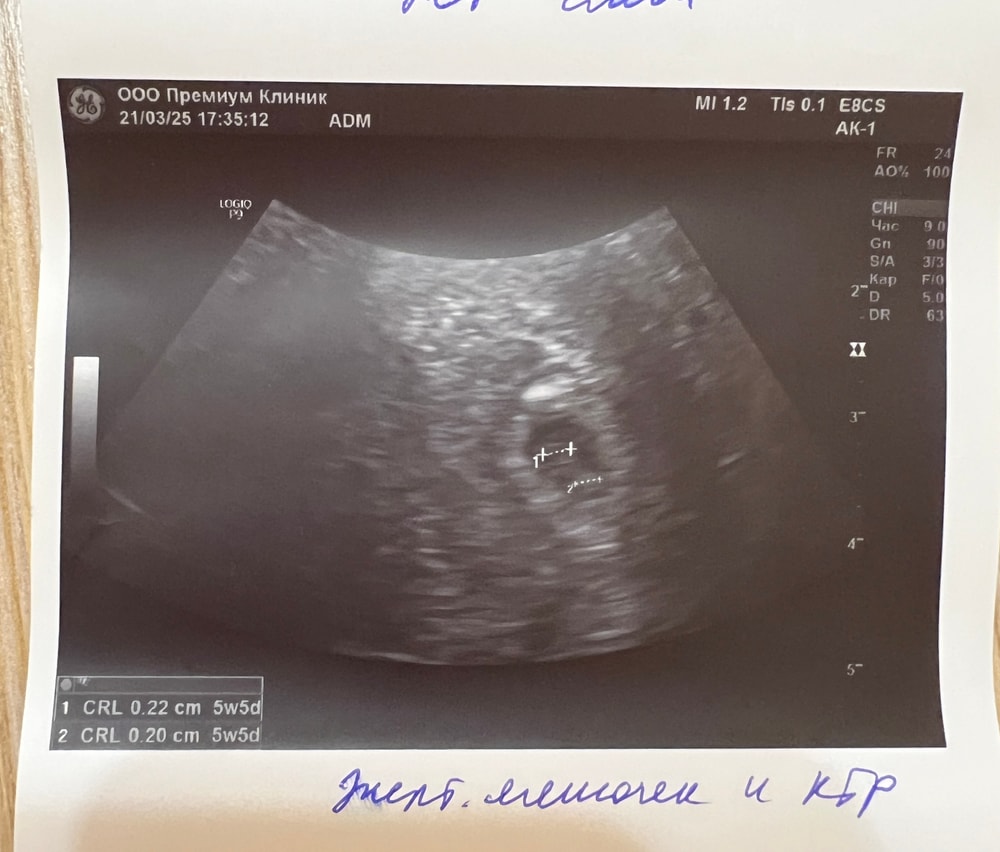

Викосик, рассказываю) нашли ПЯ Свд 6,2 мм, ктр и жм 2,2 мм. Со вторника подросло на 3 мм получается, радоваться боюсь, будем наблюдать) Изображение Изображение Изображение

Наталья, Разница между ктр и пя должна быть от 5 мм, при такой разнице как у вас, скорее всего пя остановилось в росте, а эмбрион появился вовремя. (Поэтому у вас ктр на 5.6, а пя всего лишь на 5н). В таких случаях эмбриону некуда расти, маленькое плодное яйцо его просто задавливает. При плохом росте хгч и пя плохо растет

hsnvnst, да, я уже как раз про это читаю. Что хгч медленный из за такого роста ПЯ и соответственно потом все это приводит к ЗБ из за гипоплазии ПЯ) читала, что некоторым помог Актовегин для улучшения роста ПЯ и соответственно хгч, но не знаю насколько действительно это все..